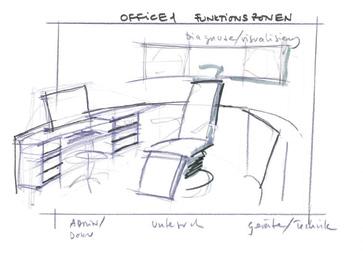

Derivate dintr-o linie lungă de modele, unităţile de tratament sunt proiectate ergonomic pentru a simplifica procedurile ENT OPD, pentru a îmbunătăţi considerabil eficienţa și a reduce oboseala utilizatorilor în camera de consultanţă / tratament ORL.

FUTURENT® III

MICRONOMIC® III